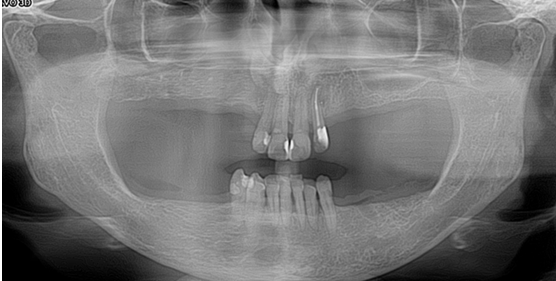

3. Ελκονεκρωτική ουλίτιδα σε έδαφος περιοδοντίτιδας

Η ασθενής ετών 29 προσήλθε στο ιατρείο μας παραπονούμενη για αυτόματη αιμορραγία και έντονο πόνο στα ούλα, αδυναμία βουρτσίσματος και μεγάλη δυσοσμία στόματος. Στην κλινική εξέταση παρατηρήθηκαν έλκη και απώλεια των μεσοδοντίων θηλών, ιδιαίτερα στα πρόσθια δόντια, καθώς και μεγάλη παρουσία μικροβιακού παράγοντα. Παράλληλα, κατά την ακτινολογική εξέταση διαπιστώθηκε οστική απώλεια ιδιαίτερα στα πρόσθια δόντια της κάτω γνάθου και στα οπίσθια άνω και κάτω γνάθου.

Μετά τη συντηρητική περιοδοντική θεραπεία, εμφανής είναι η απουσία φλεγμονής και η αποκατάσταση των μεσοδοντίων θηλών.

ΕΛΚΟΝΕΚΡΩΤΙΚΗ ΟΥΛΙΤΙΔΑ - ΑΡΧΙΚΗ ΚΑΤΑΣΤΑΣΗ

ΕΛΚΟΝΕΚΡΩΤΙΚΗ ΟΥΛΙΤΙΔΑ - ΤΕΛΙΚΗ ΚΑΤΑΣΤΑΣΗ